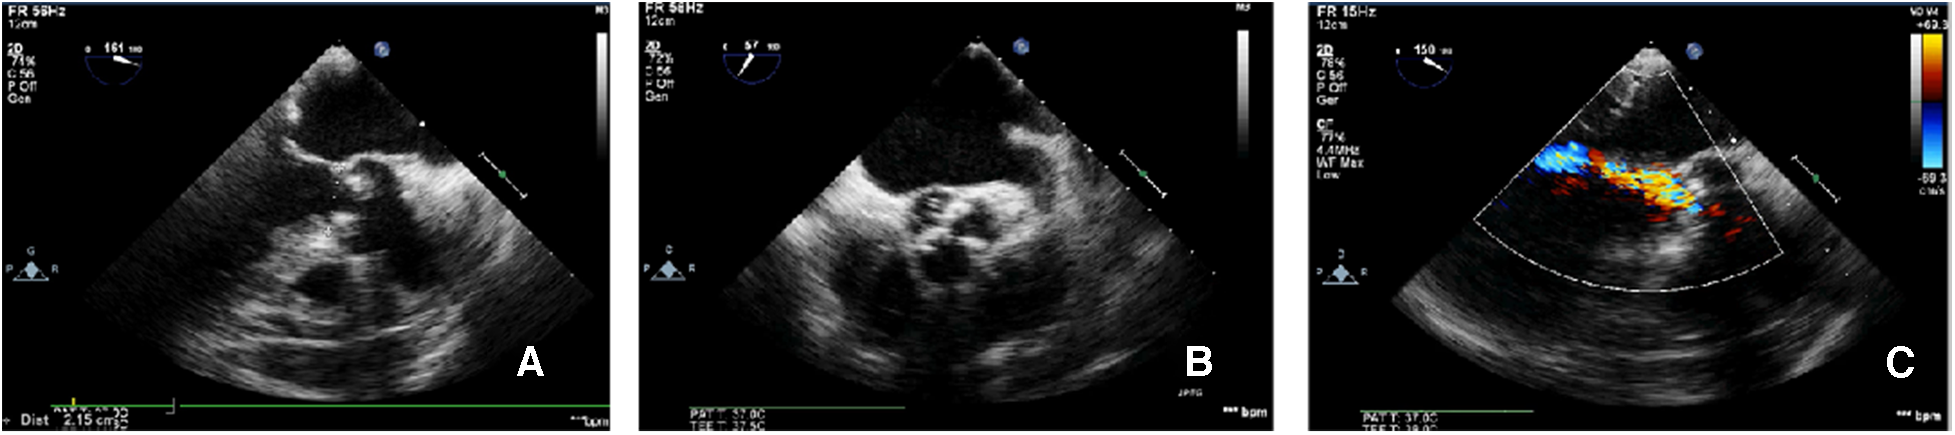

Figure 2

TEE-measured virtual valve annulus diameter. The TEE-measured virtual aortic valve annulus diameter was 21.5 mm (A); the tricuspid aortic valve leaflets were severely calcified (B); color Doppler ultrasound showed mild-to-moderate aortic valve regurgitation (C).